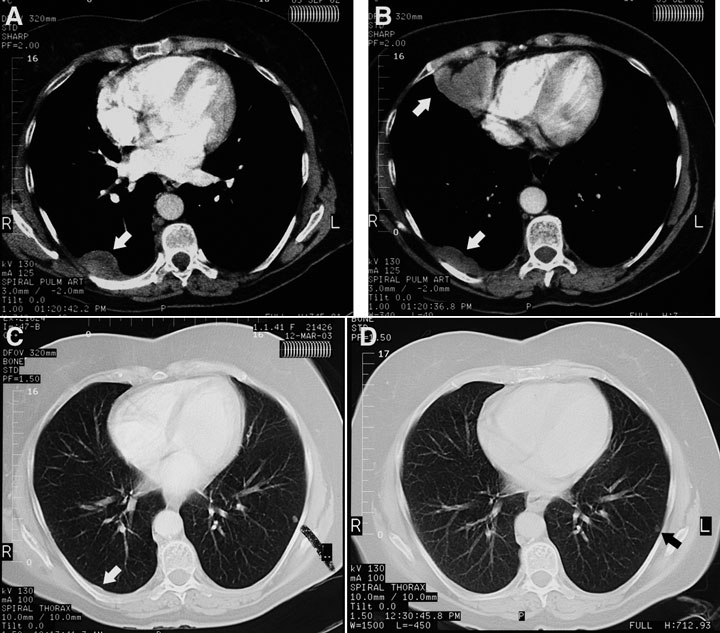

A chest radiograph taken before referral showed a pleural density measuring 10 cm × 2 cm overlying the posterior aspect of the right lower lobe, with no pleural plaques or other stigmata of asbestos exposure. A CT pulmonary angiogram performed the same day to exclude pulmonary embolism showed three pleural masses in the right side of the chest — the first corresponding to the opacity visible on the chest radiograph in the right costovertebral gutter at the level of the tracheal bifurcation, the second having a diameter of 6 cm and located in the right cardiophrenic angle (not of fatty attenuation), and the third in the right posteromedial costophrenic recess, just above the diaphragm (Box 1A and Box 1B). The lungs, mediastinum and upper abdomen (including the pancreas and para-aortic nodes) were normal.

The patient opted for no treatment, as she felt well. By 30 December 2002, a repeat CT scan of the chest showed a decrease in the size of the large, right-sided pleural mass in the costovertebral gutter from 17 mm × 9 mm (CT chest scan, 29 November 2002) to 12 mm × 6 mm. The second pleural mass was now so small it was difficult to see. The third mass was not visible, and there were two small intrapulmonary nodules — one in the right middle lobe and the other in the left lower lobe. By March 2003, the first and second pleural masses were even smaller (Box 1C) and, by June 2003, they had disappeared (Box 1D). A CT chest scan in June 2004 was normal except for the two tiny intrapulmonary nodules that had not changed in size and were probably granulomas. The patient was last reviewed in June 2007 and was in good health, with no evidence of tumour, and was scheduled for next review in 6 months.